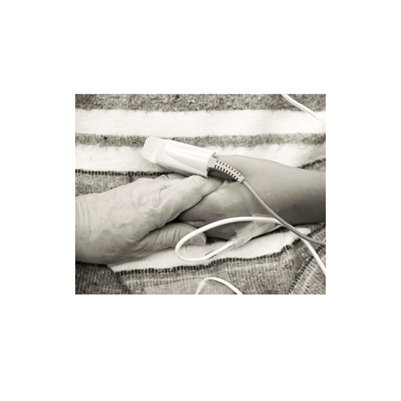

Darkness into the Light. In 2012, The Amazon Project gave eye care to nearly 6000 patients within a 200 kilometer radius of their base in Leticia, Colombia.